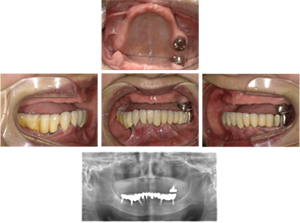

60代 女性 全顎 インプラント サイナスリフト等

| 年代・性別 | 60代・女性 |

| 主訴 | 上顎の入れ歯が割れた。リンゴやおかきを食べられるようになりたい。 |

| 部位 | 右上④3②・左上②3④5⑥のブリッジ |

| 治療期間 | 2年 |

| 費用 | ¥2,447,500(税込) |